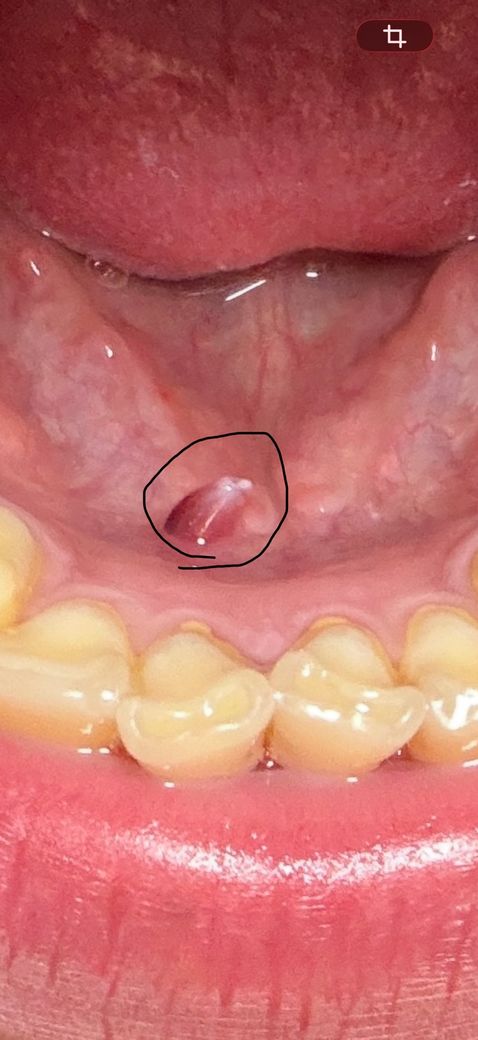

한 2~3주정도 계속 저 물집이있는데 병원가서 제거를 해야될까요?? 정체가 멀까요?ㅠ 자세히 본건 너무 무섭습니다 ㅠㅜ 답변 꼭 부탁드릴께요 ㅜㅜㅠ

날카로운 음식이나 물체에 해당 부분이 자극되어 나타난 것이 아니고 갑자기 나타났다면 구강 내 연조직 문제를 생각해보아야 합니다. 해당 위치는 타액선이 위치한 곳이므로 해당 부분의 문제가 있는지도 평가해야 합니다. 일반적인 치과가 아닌 구강내과 전문의가 상주하는 치과나 대학병원 내 구강내과를 방문해보시길 바랍니다.

혈종으로 보입니다 잘못 씹어서 생긴 상처에 피가 안에서 고인 것 같은데 정확한건 치과를 가봐야 압니다 구강내과로 가보시는 것을 추천합니다